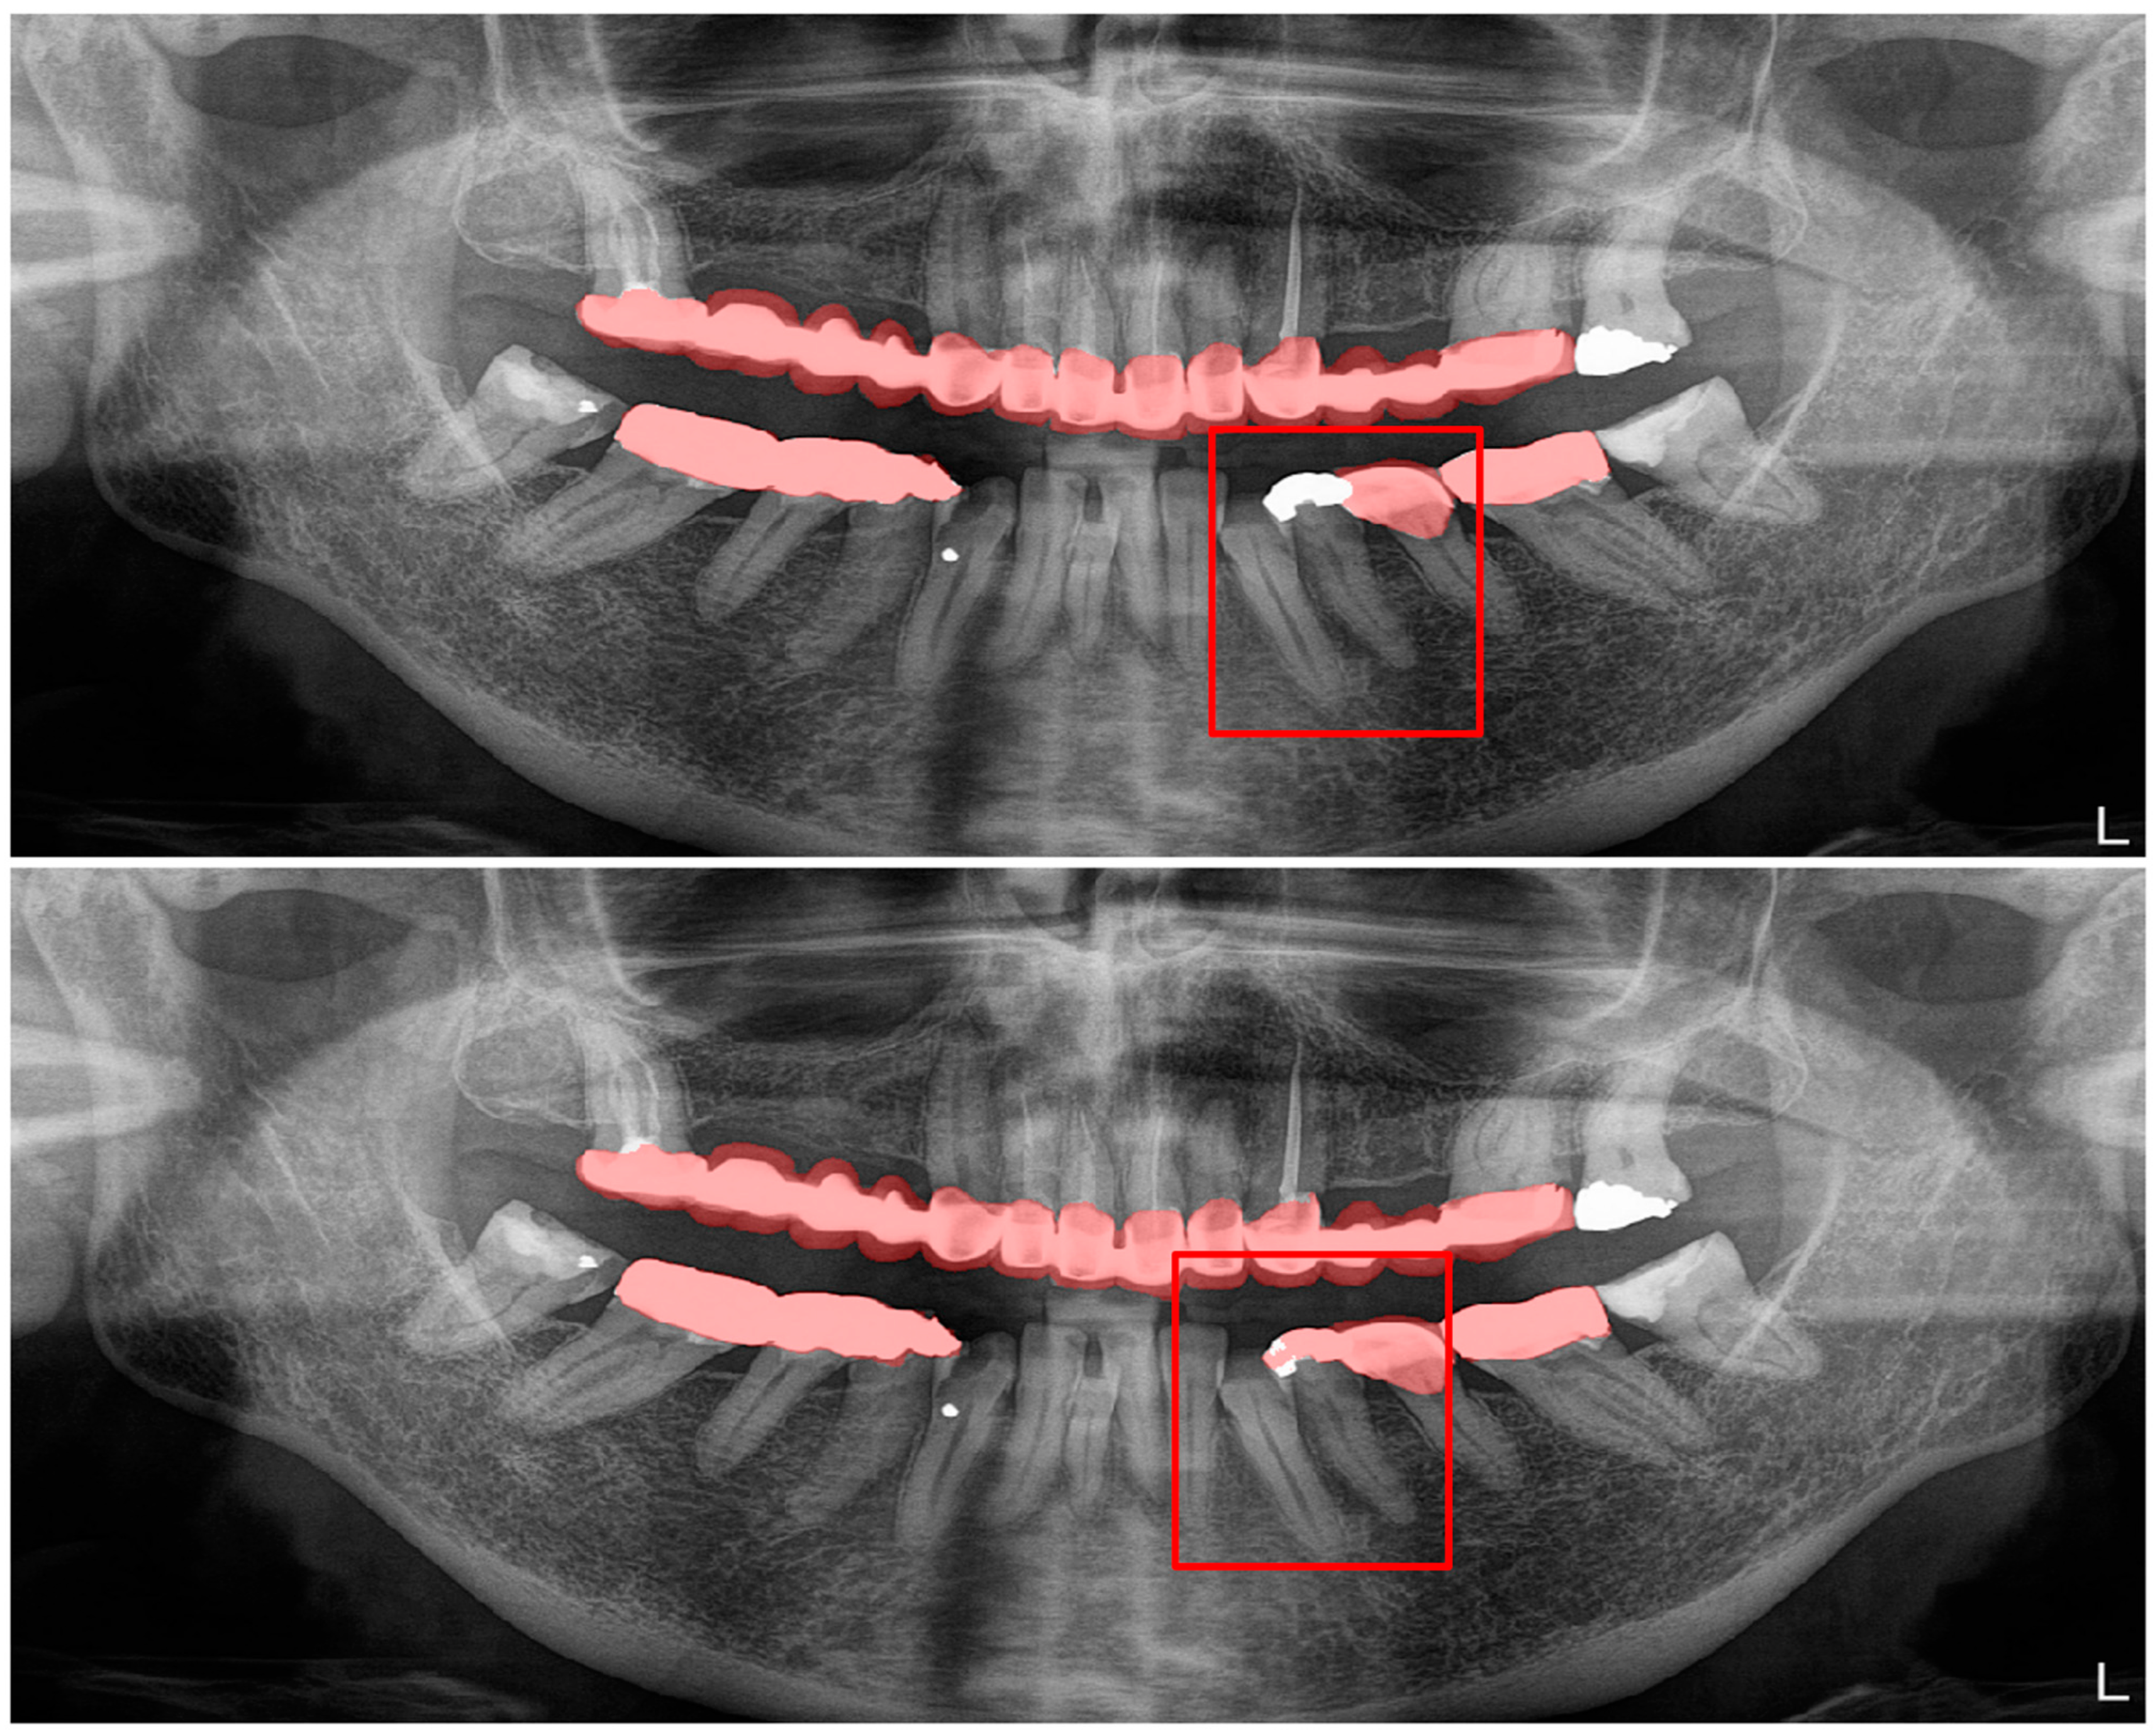

Figure 7.

Automatic segmentation of residual roots. Manual segmentation (upper image) and automatic segmentation (lower image) can be seen above.

Figure 10.

A wide amalgam restoration in the mandibular left first premolar tooth was mis-segmented as a crown restoration. Manual segmentation (upper image) and automatic segmentation (lower image) can be seen above.

In root canal filling segmentations, the number of erroneous situations were higher than the rest of the segmentations as there were multiple limitations. The pitfalls in automatic segmentation for this study’s dataset of the root canal fillings were as follows: inadequate fillings that were carried out with a single or several gutta-perchas, root canal fillings of multirooted teeth that were superimposed with an adjacent tooth, gutta-perchas that did not extend through the entire root canal, and cases in which the restoration in the pulp chamber was misinterpreted and segmented as gutta-percha; however, despite these three limitations, it was seen that the automatic segmentation of our model had more precise and sharply demarcated segmentations than the radiologists did. In root canal filling segmentations, the only limitation was related to the superimpositions, as the residual roots that were superimposed with the neighboring structures were not automatically segmented by our model.